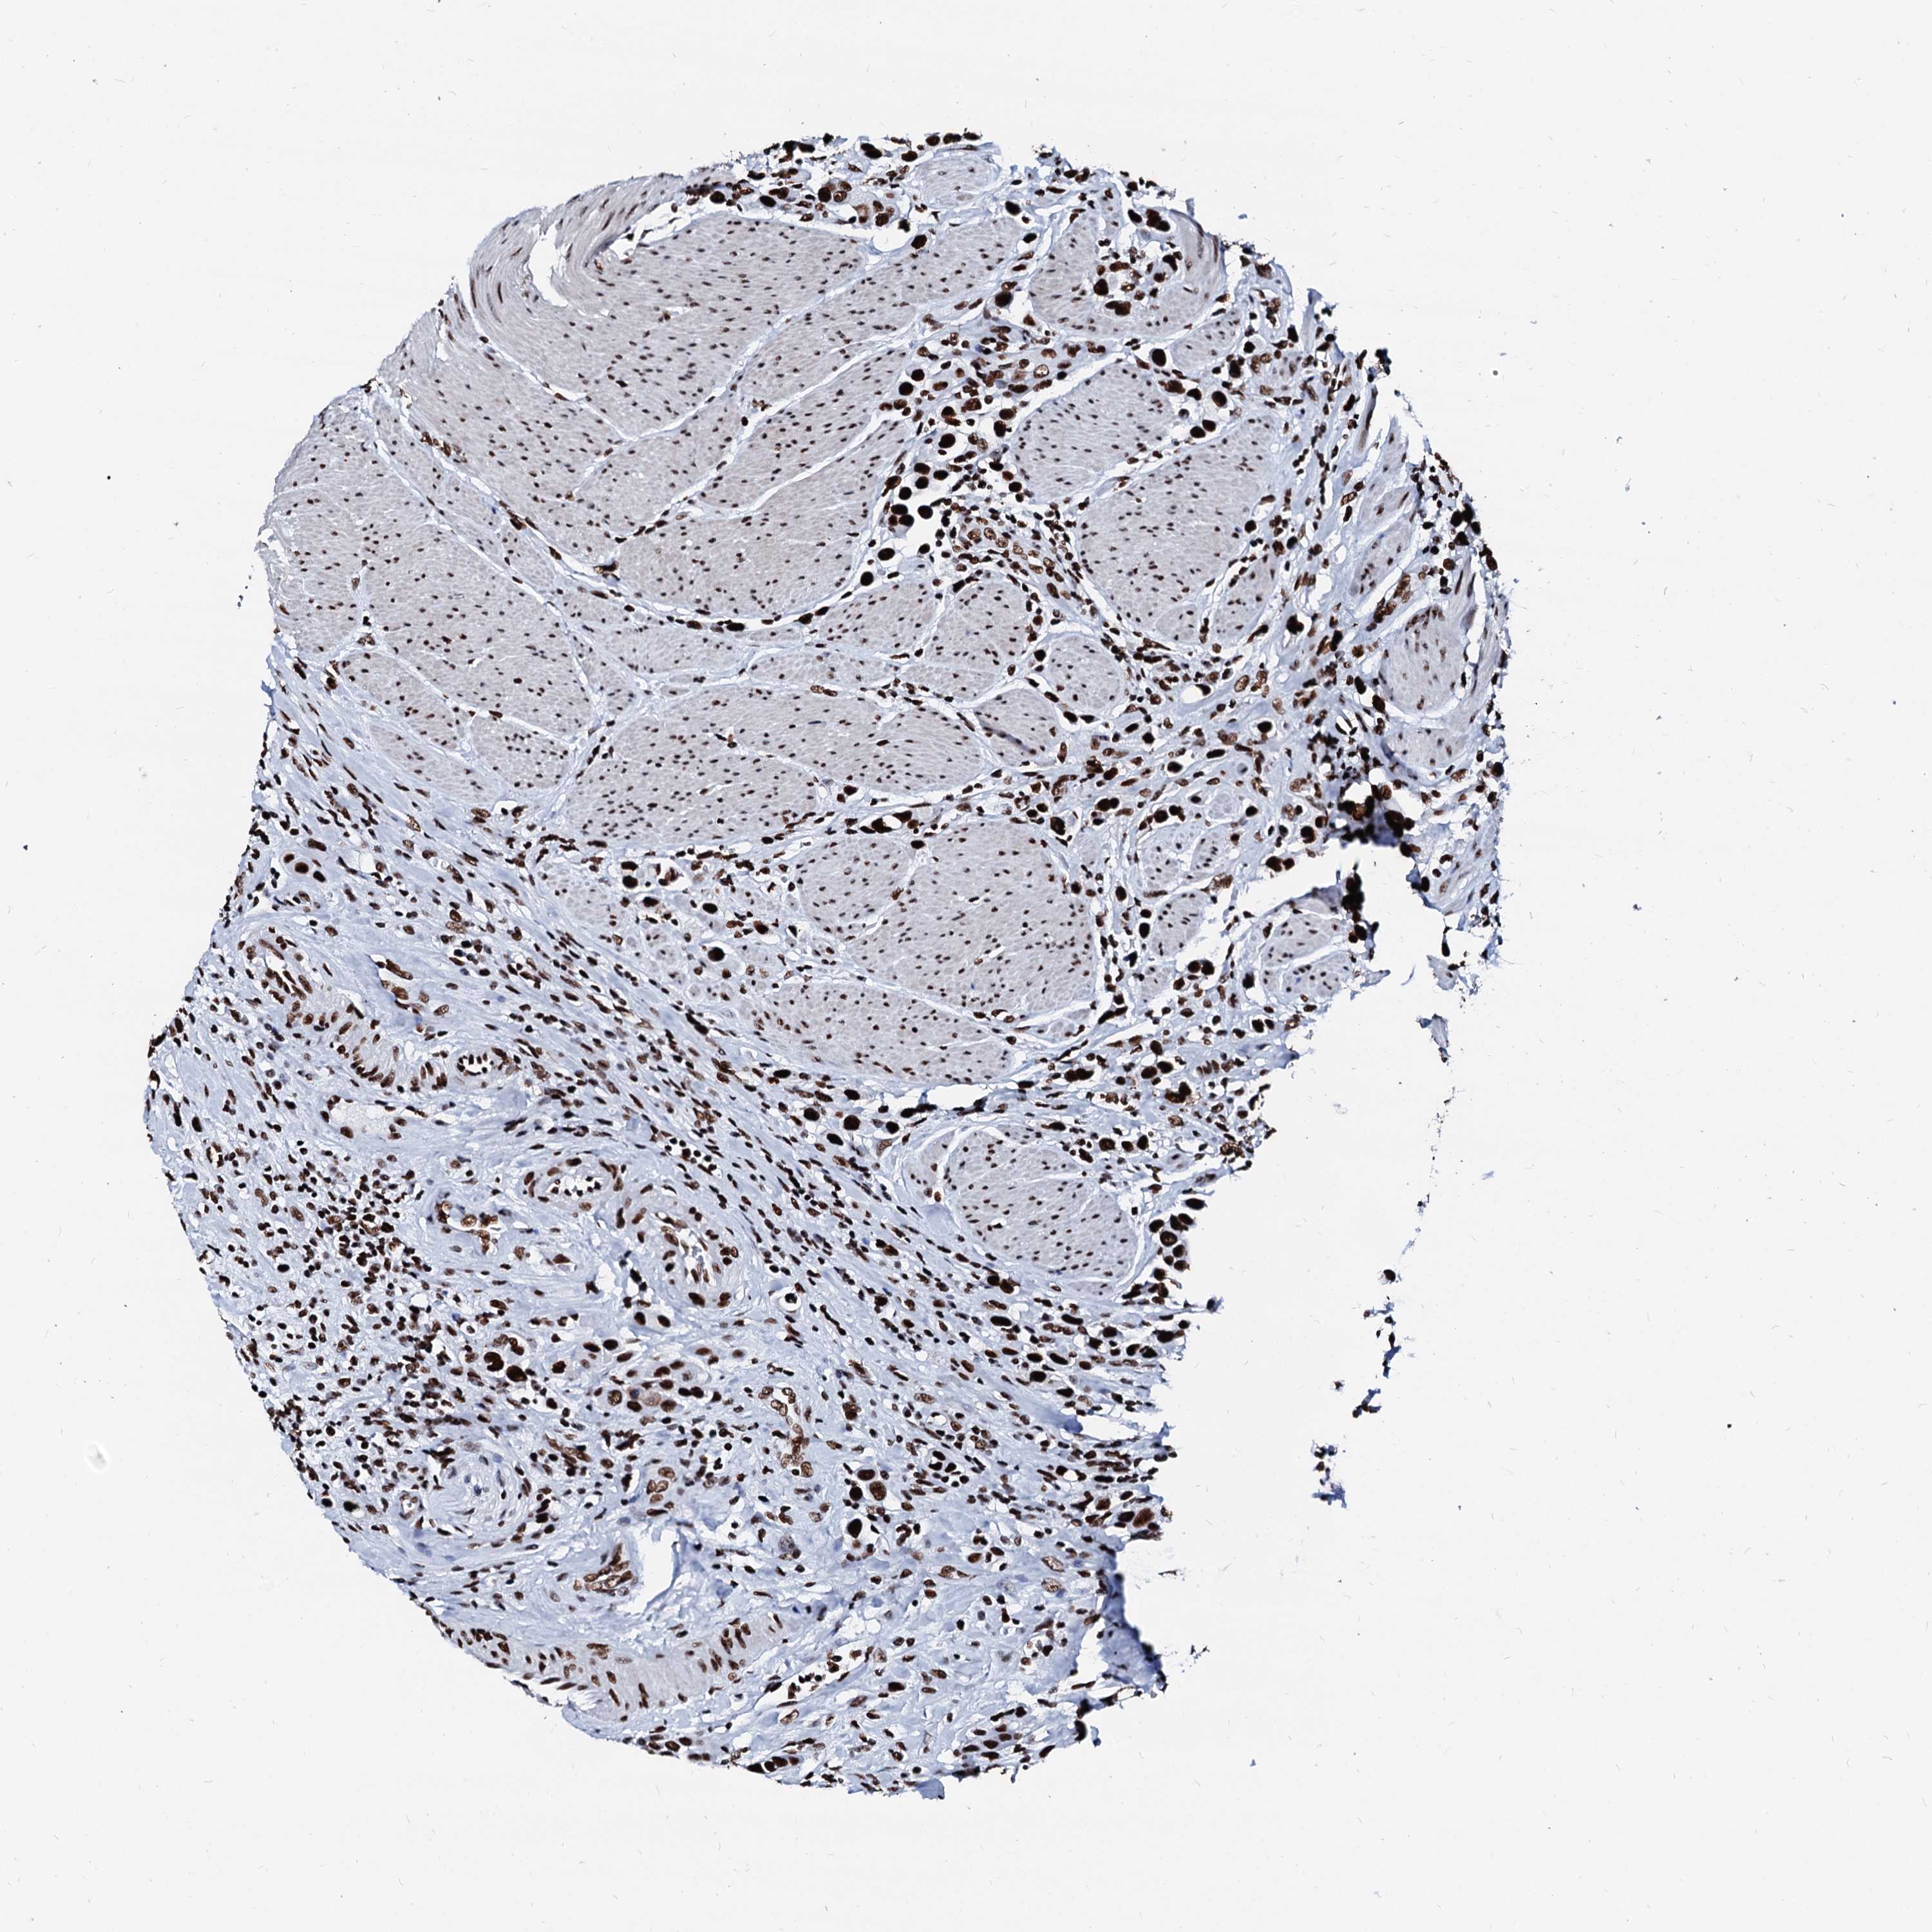

UROTHELIAL CANCER - Protein expressioni

A mouse-over function shows sample information and annotation data. Click on an image to view it in a full screen mode. Samples can be filtered based on level of antibody staining by selecting one or several of the following categories: high, medium, low and not detected. The assay and annotation is described here.

Antibody stainingi

Antibody staining in the annotated cell types in the current human tissue is reported as not detected, low, medium, or high, based on conventional immunohistochemistry profiling in selected tissues. This score is based on the combination of the staining intensity and fraction of stained cells.

Each image is clickable and will lead to virtual microscopy that enables deeper exploration of all samples and also displays staining intensity scores, fraction scores and subcellular localization as well as patient and tissue information for each sample.

Antibody HPA040971

Antibody HPA043614

Staining

High

Medium

Low

Not detected

Intensity

Strong

Moderate

Weak

Negative

Quantity

>75%

75%-25%

<25%

None

Location

Nuclear

Cytoplasmic/membranous

Cytoplasmic/membranous,nuclear

Urothelial carcinoma, Low grade